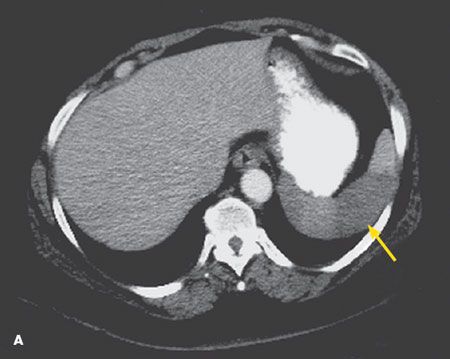

An abdominal CT scan revealed a focal, 5-cm, wedge-shaped area of decreased density in the anterior aspect of the spleen in axial view (A, arrow) and coronal view (B, arrow). This finding is consistent with splenic infarction.